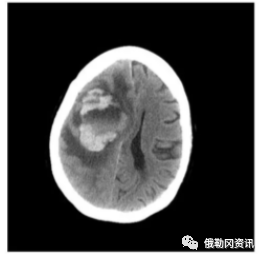

该女性因癫痫发作送往医院治疗,做了检查医生怀疑脑部有肿瘤。但在手术期间,却发现原来片子里疑似肿瘤的部分,其实是食脑虫在“作怪”。

这块如高尔夫球大小一般的糊状血块,就是“食脑虫”吞噬脑细胞的地方。